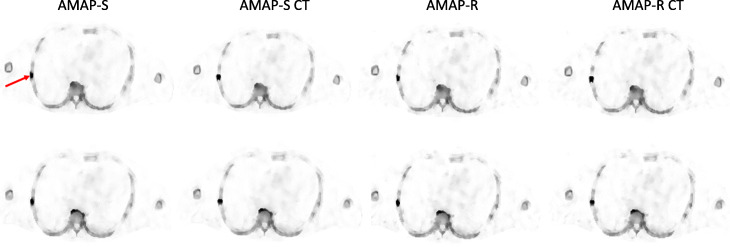

Fig. 4.

Example reconstructed SPECT transverse slice for AMAP-S and AMAP-R with and without the 5-mm SPECT/CT mismatch at the level of rib lesion of the male patient study with artificial lesions. Red arrow shows the lesion location. AMAP-S and AMAP-R refer to reconstructions, where lesion is absent in the CT, AMAP-S CT, and AMAP-R CT to lesion-present cases. Top row shows aligned cases and bottom row reconstructions with the 5-mm SPECT/CT mismatch. The color scale is set to SUV 15 for all images

The effect of SPECT/CT position mismatch is presented in Table 3. AMAP-S and AMAP-R reconstructions are more sensitive to SPECT/CT mismatch than OSEM or RDP. This is especially true for reconstructions with matching CT lesions. The difference generated by the 5-mm mismatch is however difficult to appreciate visually as shown in Figs. 4 and 5.

Reconstruction with anatomical prior is susceptible to misalignments between the anatomical and emission images to a greater extent than reconstruction without anatomical prior, and this was also observed in our study. Table 3 shows that SPECT/CT misalignment has a significantly bigger effect on lesion SUVs when AMAP-S or AMAP-R is used compared to OSEM or RDP. Therefore, careful attention must be paid to the SPECT/CT alignment when using AMAP-S and AMAP-R, more so than is typically the case when CT is used only for attenuation and scatter compensations. Fortunately, SPECT/CT misalignments in bone SPECT/CT studies are usually less than 5 mm [3], which according to Figs. 4 and 5 do not produce artifacts which can be visually detected.